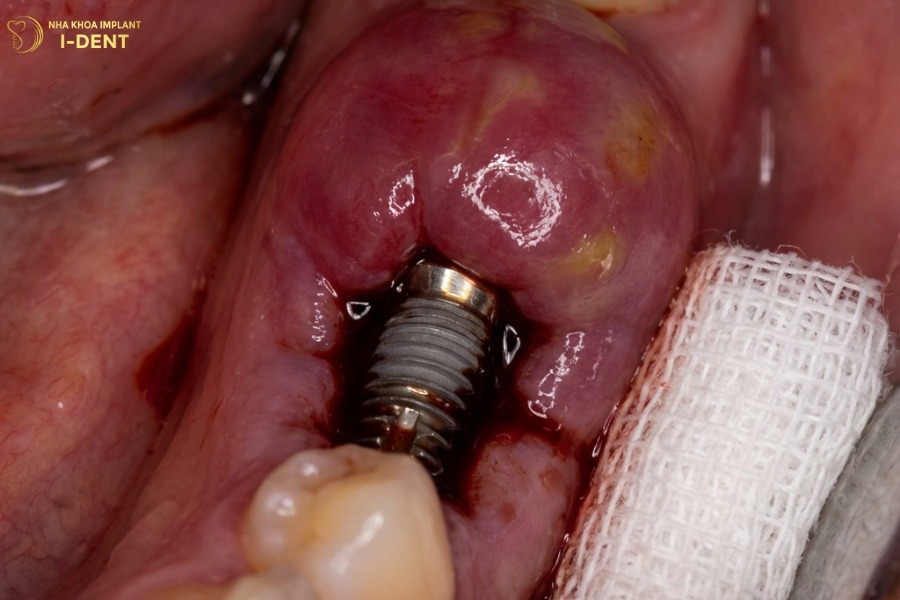

Tích hợp xương thất bại

Tích hợp xương thất bại xảy ra với tỷ lệ 2-5%, khiến implant không liên kết được với xương hàm và cần cấy lại. Nguyên nhân bao gồm chất lượng xương kém, mật độ xương thấp, bệnh nhân hút thuốc lá nặng, tiểu đường không kiểm soát, bị nhiễm trùng trong giai đoạn tích hợp hoặc implant bị quá tải lực quá sớm. Dấu hiệu của thất bại tích hợp xương là răng implant bị lung lay khi kiểm tra, đau khi chạm vào hoặc có khoảng trống giữa implant và xương trên phim X-quang. Khi xảy ra thất bại tích hợp xương, bác sĩ sẽ tháo implant, chờ xương lành trong 3-4 tháng rồi cấy lại.

Quá trình tích hợp xương thất bại khi cấy ghép implant biểu hiện rõ nhất khi chụp X-Quang.